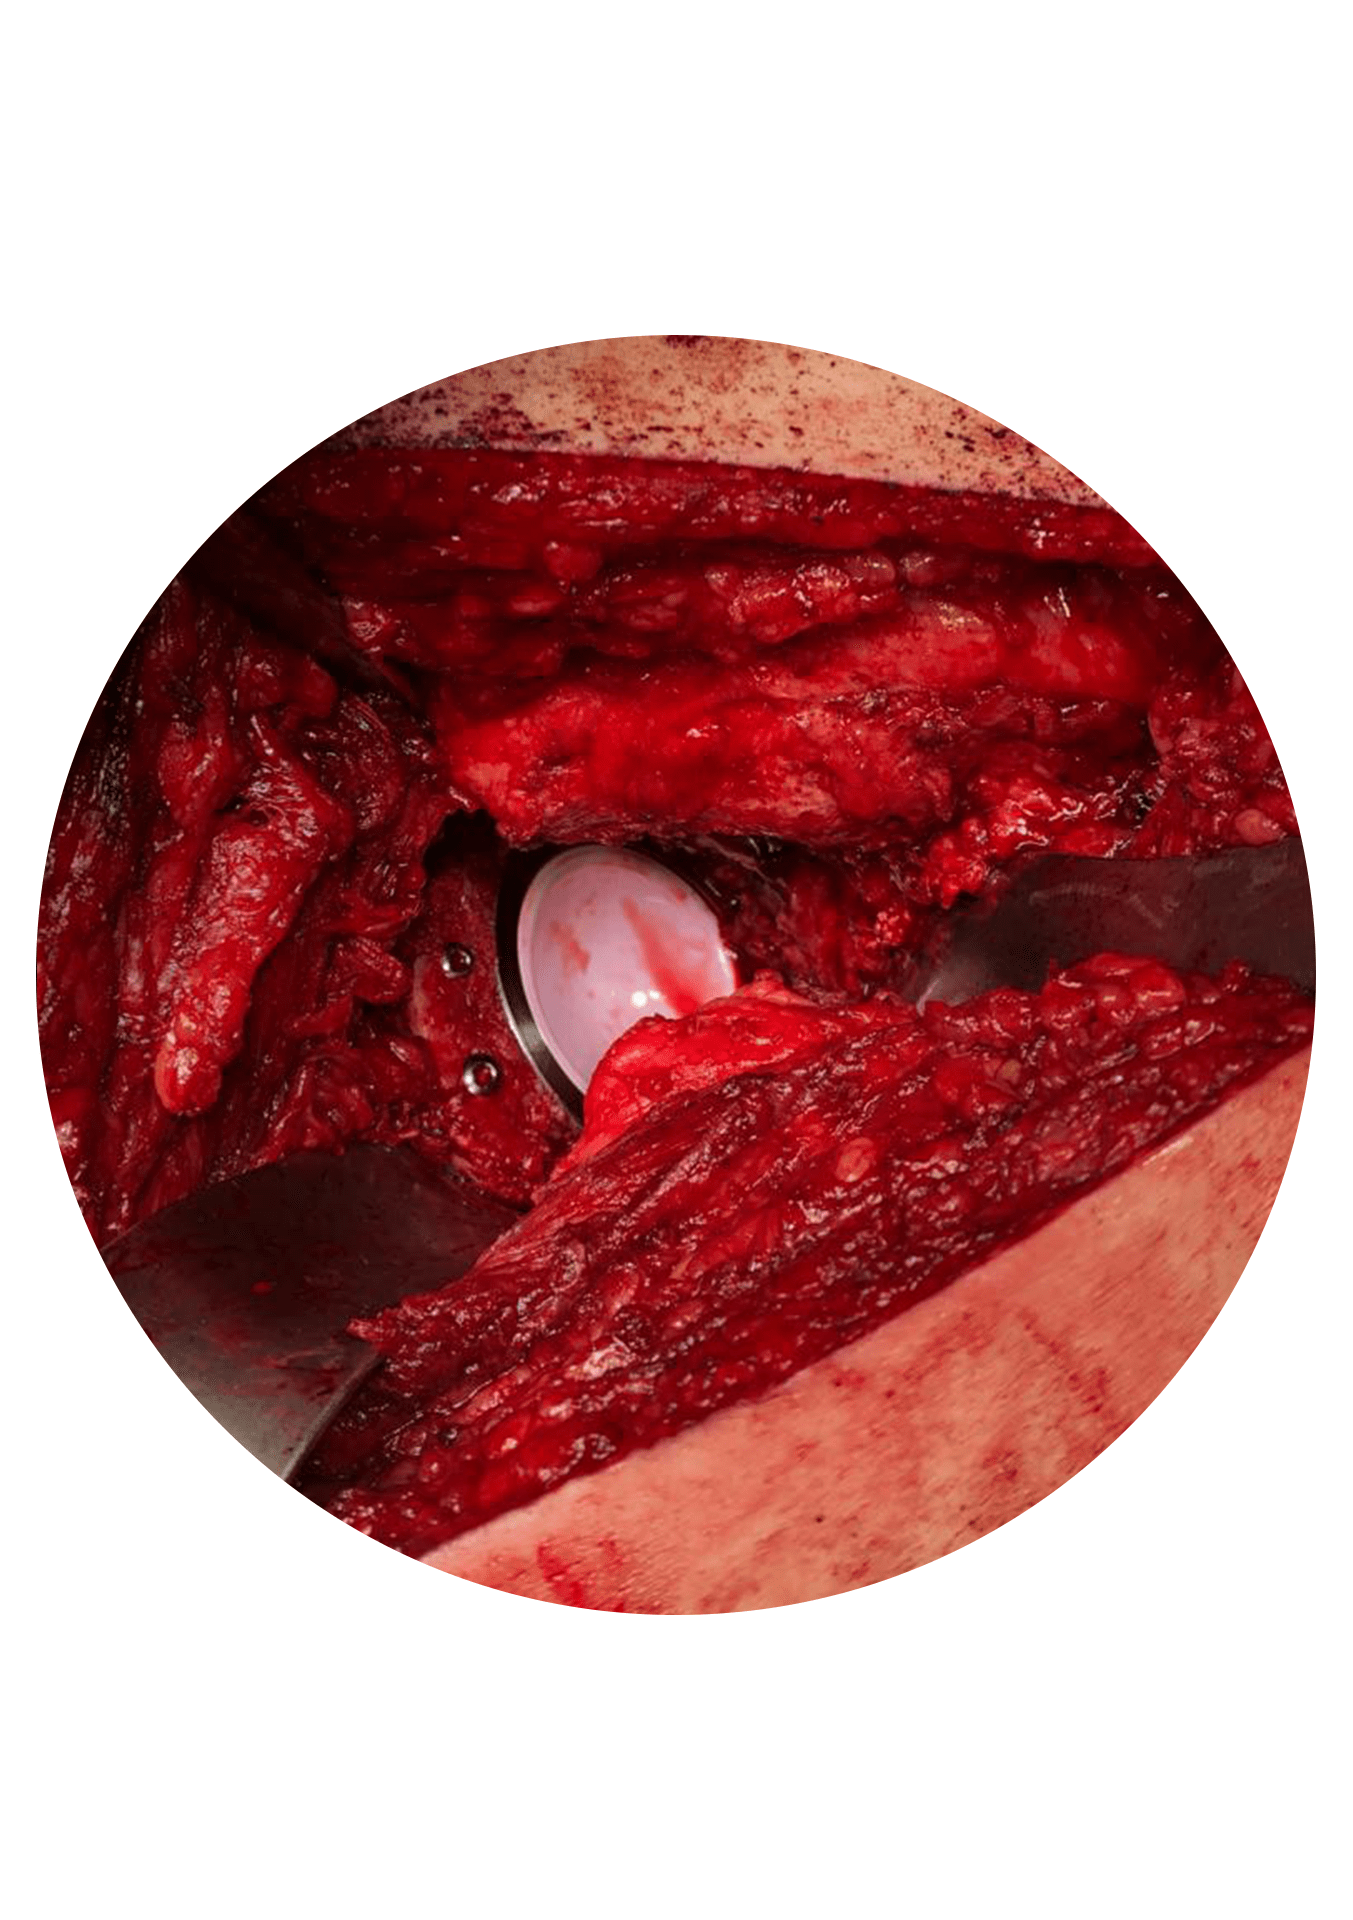

Primeiro: remoção do implante(s) deficiente(s) e preservação dos implantes competentes. Este é muitas vezes o momento mais complexo da cirurgia de revisão. O seu objetivo principal é remover apenas os implantes que precisam de ser substituídos e neste processo causar a menor lesão possível na estrutura óssea da articulação para facilitar a fase seguinte.

Segundo: reconstrução da “nova” articulação. Embora o momento da remoção dos implantes seja importante no resultado da cirurgia de revisão, esta é na sua essência uma cirurgia de reconstrução.